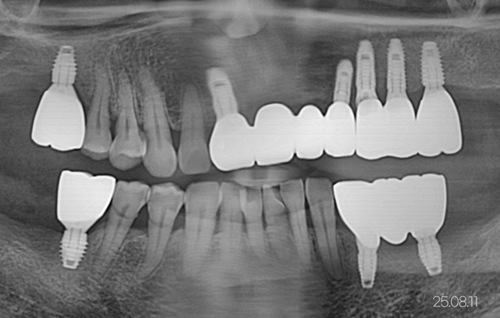

60대 임플란트 예시 이미지 25.08.11 / 본 칼럼의 이해를 돕기 위해 본원에서 진료한 분의 동의 후 게시하였습니다. 진료 결과는 개인에 따라 붓기, 출혈, 통증이 생길 수 있어 주치의와 충분히 의논한 후 결정하시기 바랍니다.